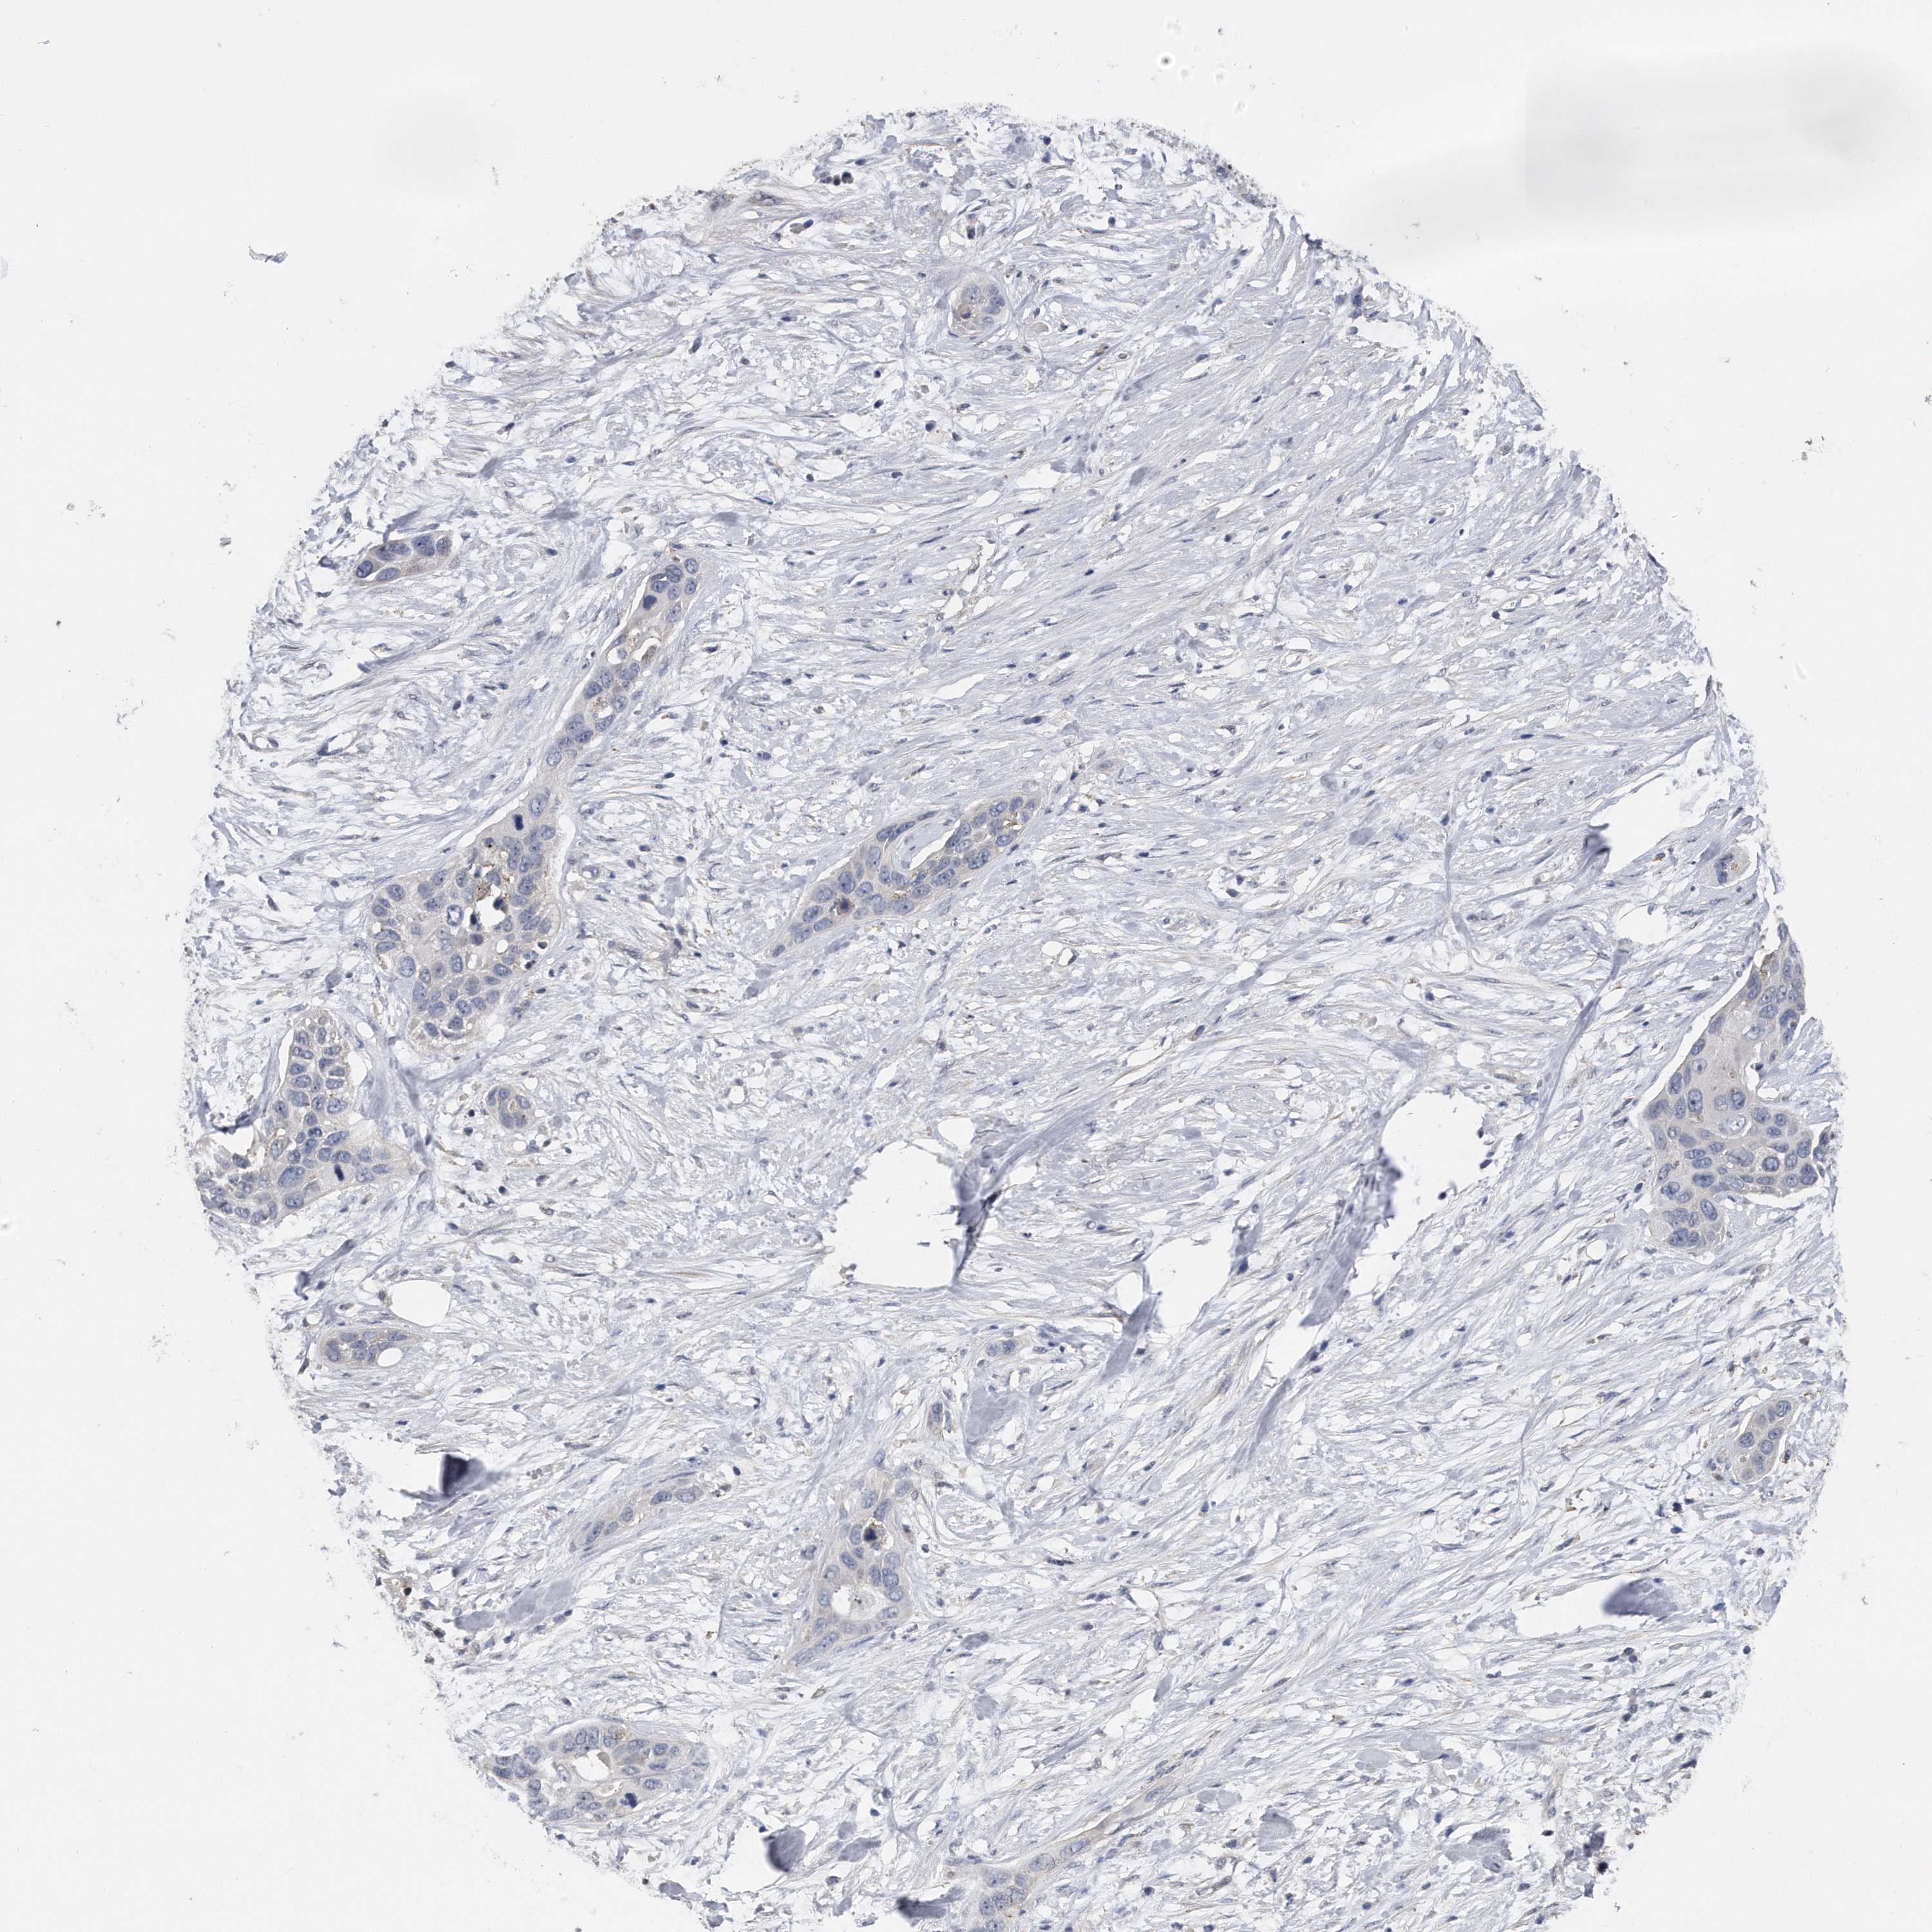

PANCREATIC CANCER - Protein expressioni

A mouse-over function shows sample information and annotation data. Click on an image to view it in a full screen mode. Samples can be filtered based on level of antibody staining by selecting one or several of the following categories: high, medium, low and not detected. The assay and annotation is described here.

Note that samples used for immunohistochemistry by the Human Protein Atlas do not correspond to samples in the TCGA dataset.

Antibody stainingi

Antibody staining in the annotated cell types in the current human tissue is reported as not detected, low, medium, or high, based on conventional immunohistochemistry profiling in selected tissues. This score is based on the combination of the staining intensity and fraction of stained cells.

Each image is clickable and will lead to virtual microscopy that enables deeper exploration of all samples and also displays staining intensity scores, fraction scores and subcellular localization as well as patient and tissue information for each sample.

Antibody HPA029452

Staining

High

Medium

Low

Not detected

Intensity

Strong

Moderate

Weak

Negative

Quantity

>75%

75%-25%

<25%

None

Location

Nuclear

Cytoplasmic/membranous

Cytoplasmic/membranous,nuclear

Adenocarcinoma, NOS